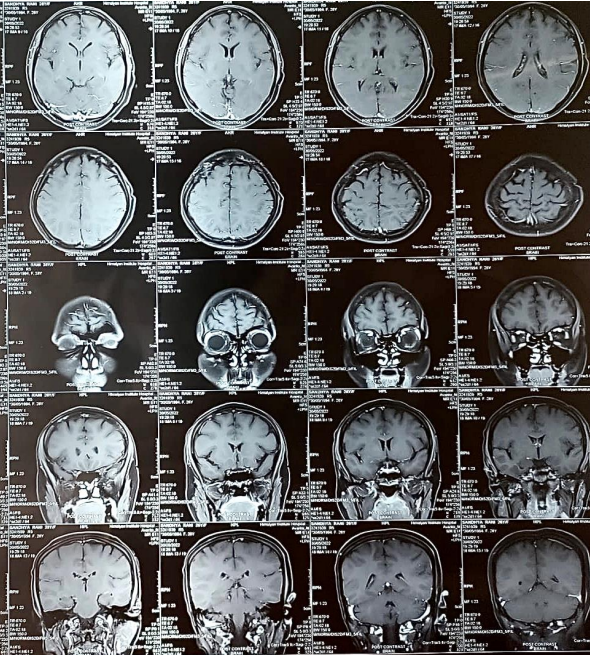

Figure 1. MRI Brain imaging showing 1.5 x 1.5 mm and 2 x 2 mm focal blooming in the left insular cortex and left frontal lobe respectively which were suggestive of calcified granuloma.No active metastatic lesion seen.

Figure 2. MRI Brain imaging showing 1.5 x 1.5 mm and 2 x 2 mm focal blooming in the left insular cortex and left frontal lobe respectively which were suggestive of calcified granuloma. No active metastatic lesion seen.

A 28-year-old female presented to the medical oncology department with complaints of progressive severe headache, multiple episodes of vomiting and generalized weakness. Her past medical history was notable for triple-negative breast cancer with liver and adrenal metastasis that was diagnosed approximately 5 months prior. She was undergoing treatment with chemotherapy (4 cycles of doxorubicin and cyclophosphamide-based chemotherapy followed by taxane-based chemotherapy) when after her 5th cycle (1st taxane), she developed a severe headache. Radiologic studies were performed in the department. MRI Brain was done which showed 1.5 x 1.5 mm and 2 x 2 mm focal blooming in the left insular cortex and left frontal lobe respectively which were suggestive of calcified granuloma. A lumbar puncture with a cerebrospinal fluid analysis revealed the presence of malignant cells. Together with clinical features and cerebrospinal fluid findings, leptomeningeal carcinomatosis was diagnosed. This case report presents an uncommon but well-known complication of breast cancer ~ Leptomeningeal carcinomatosis.

A 28-year-old female nonsmoker presented to the medical oncology department with progressively worsening headache, multiple episodes of vomiting and generalized weakness. Five months prior, she was diagnosed with right-breast triple-negative Infiltrating ductal carcinoma grade II (TNBC) with liver and adrenal metastasis. She was started on chemotherapy with doxorubicin, cyclophosphamide followed by paclitaxel. However During the course of her treatment, after the first taxane(5th cycle of chemotherapy), she developed a severe headache and multiple episodes of vomiting. Magnetic resonance imaging (MRI) of the brain with contrast was obtained. MRI showed 1.5 x 1.5 mm and 2 x 2 mm focal blooming in the left insular cortex and left frontal lobe respectively which were suggestive of calcified granuloma. However, the patient’s clinical picture was concerning for the development of metastatic central nervous system (CNS) disease however MRI Brain did not correlate with the clinical picture. Given the patient’s clinical history and new